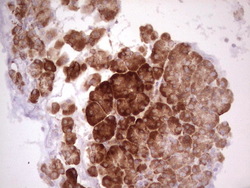

- Main image

- Experimental details

- Immunohistochemical staining of paraffin-embedded Human lymphoma tissue using anti-WIBG mouse monoclonal antibody. (Heat-induced epitope retrieval by 1 mM EDTA in 10mM Tris, pH8.5, 120C for 3min, TA806496)

- Validation comment